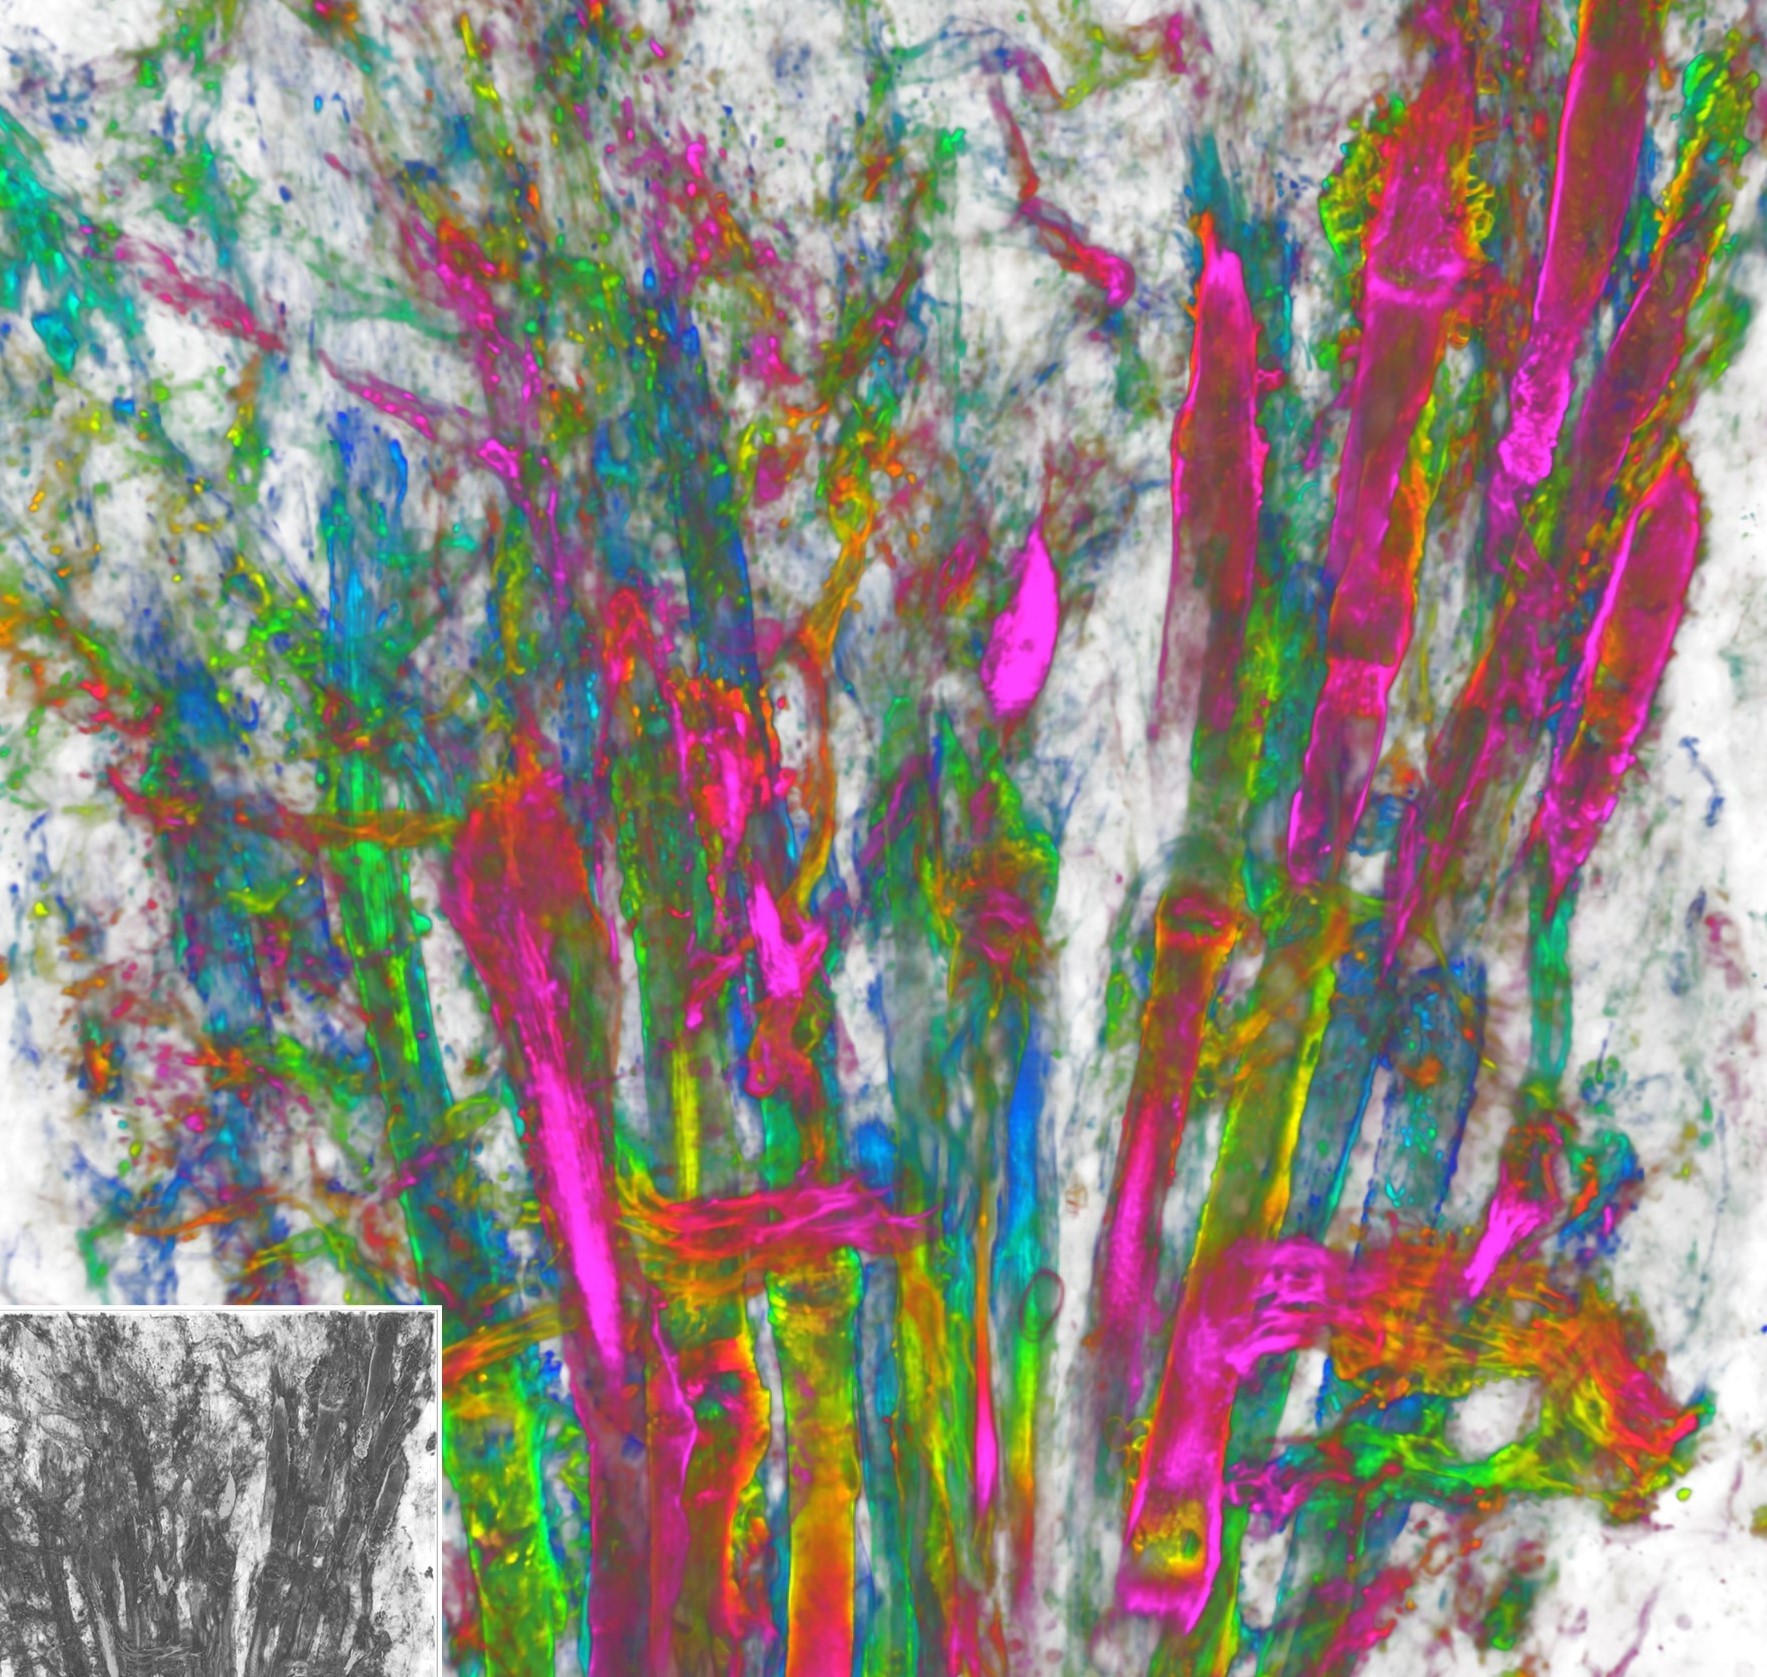

We systematically investigate the in vivo behavior and fate of drug delivery systems using advanced imaging and analytical tools, including intravital fluorescence microscopy, transmission electron microscopy, and synchrotron radiation-based imaging. Our studies focus on how delivery systems interact with physiological and immune barriers, such as the mononuclear phagocyte system (especially in the liver and spleen), vascular endothelium, and immune cell subsets. We analyze circulation kinetics, biodistribution profiles, cellular uptake mechanisms, and clearance pathways to elucidate the principles that govern delivery efficiency and target-site accumulation. These mechanistic insights guide the rational optimization of carrier design to improve therapeutic precision and minimize systemic toxicity.